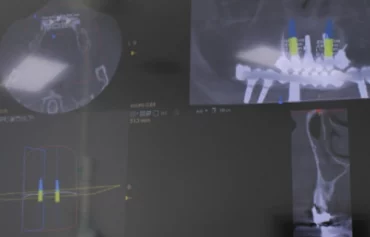

Nuestro equipo liderado por el Dr. Hugo Conza está altamente capacitado y cuenta con una amplia experiencia en este campo. Utilizando las últimas tecnologías 3D y técnicas avanzadas más innovadora, el Dr. Hugo Conza y su equipo te ofrecen un diagnóstico preciso y detallado, garantizando resultados impecables en cirugías dentales complejas y tratamientos de implantología.